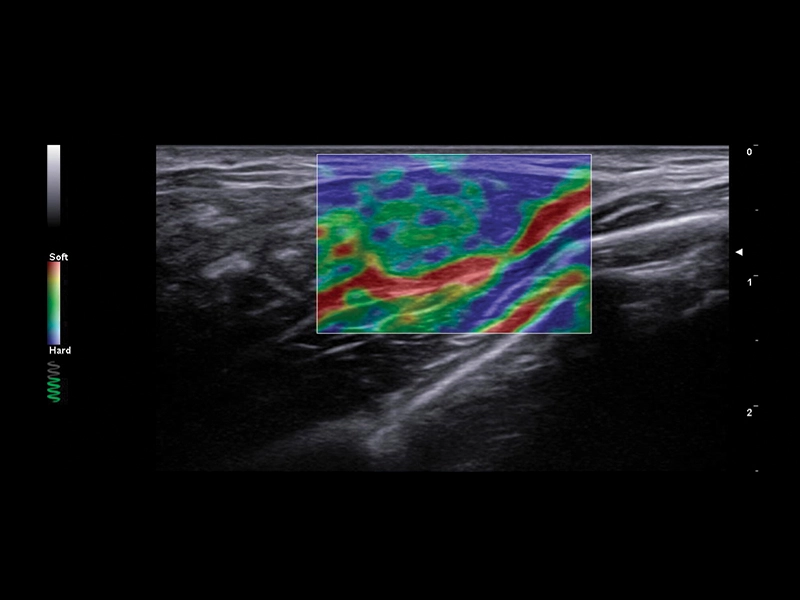

MyLab™C25 - ElaXto in breast

MyLab™C25 - ElaXto in breast